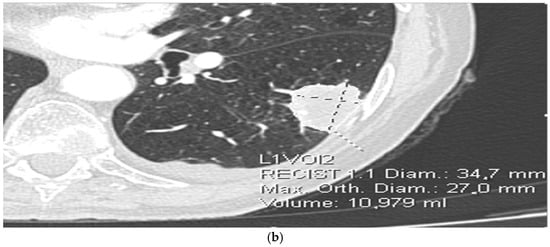

2.3. Radiomics Extraction from CT Images

- Lesion morphology: maximum diameter (mm), volume (mm3), shape irregularity;

- Texture features: mean attenuation, entropy, skewness, kurtosis, gray-level co-occurrence metrics;

| Diameter of the tumor * | 35.4 (15.8–102.6) | 35.6 (15.8–72.0) | 34.6 (17.8–102.6) | 0.588 |

| Volume of the tumor * | 11.468 (1.565–217.276) | 11.588 (1.565–158.455) | 11.935 (1.851–217.276) | 0.985 |